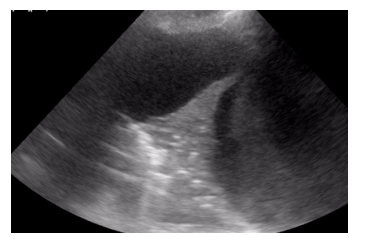

O exame físico do hemitórax esquerdo de um paciente internado na enfermaria de clínica médica, com dispneia, revelou: ausculta abolida, frêmito toracovocal abolido, percussão maciça. O POCUS realizado em transição toracoabdominal evidencia a imagem a seguir.

Com base nessa situação hipotética, é correto afirmar que a alteração patológica percebida no exame físico e no exame complementar trata-se de